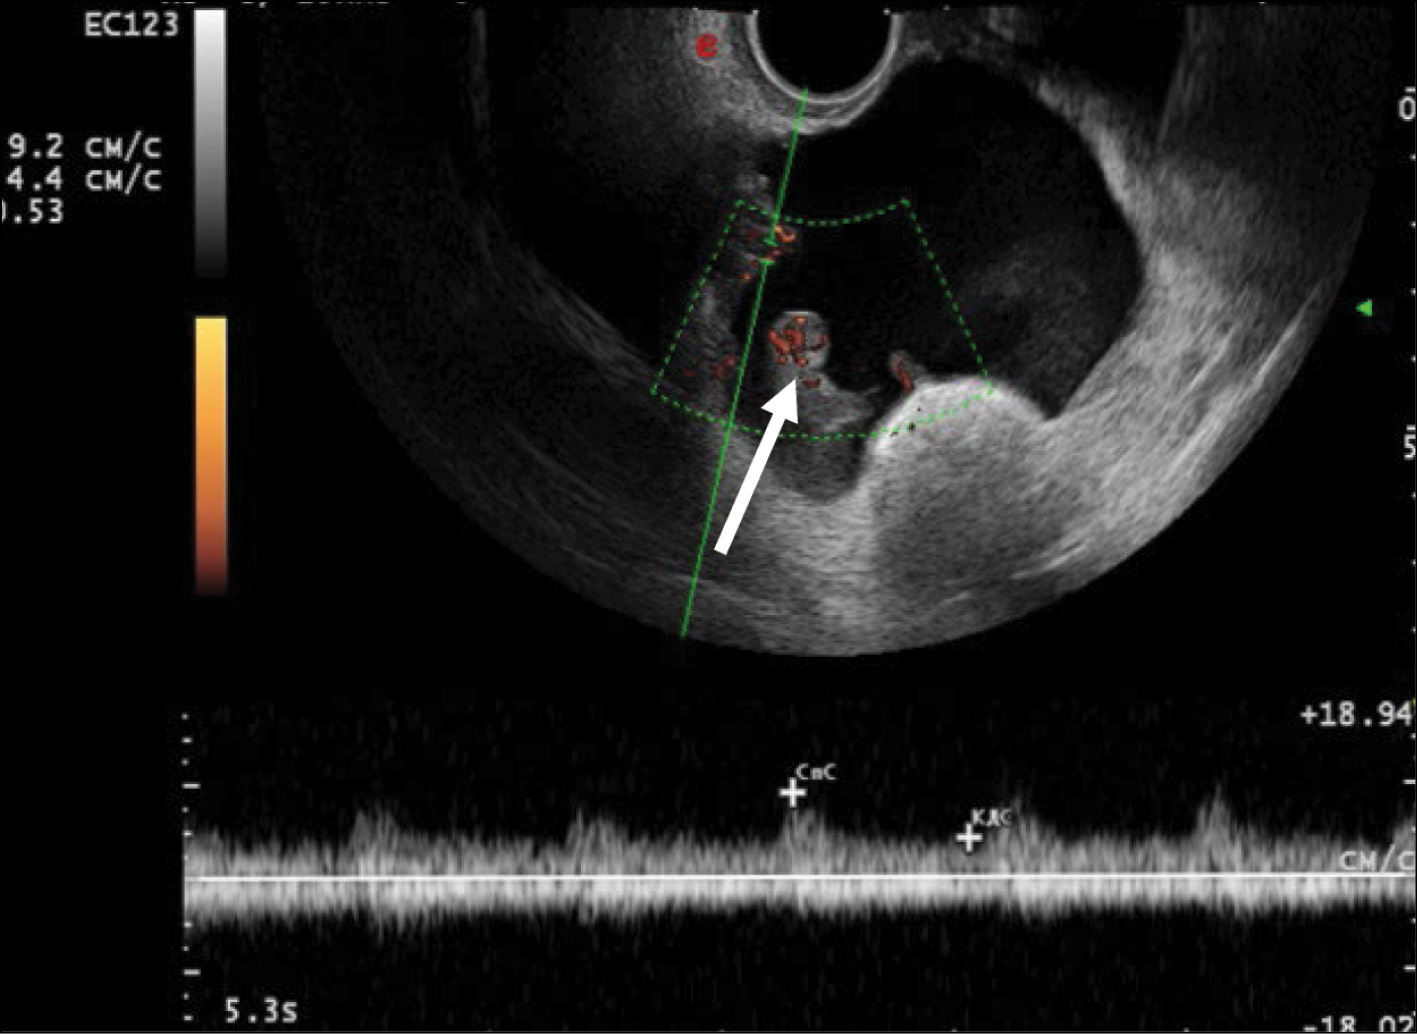

Malignant struma of the right ovary was detected 2 years after surgical treatment of primary benign struma of the left ovary. Six months later, the patient was diagnosed with a disease relapse, visualized exclusively according to radioisotope research methods. In the fourth year of anticancer treatment, ultrasonography revealed recurring foci along the peritoneum. According to the ultrasound data on the pelvic peritoneum and the projection of the removed right ovary, multiple solid nodes with high blood flow were visualized. Peak systolic velocity ranged from 2 to 9 cm/s in minor lesions from 4 to 12 mm, with an RI max of 0.53. For 4 years, the patient underwent radioiodine therapy with 131I with an activity of 6.0 GBq; the patient’s condition during the treatment was satisfactory.

US demonstrated that the recurrent lesion of malignant struma ovarii along the pelvic peritoneum, identified in the presence of ascites, had an iso-hypoechoic structure with fuzzy contours and small size (4–12 mm). The peritoneum of the small pelvis outside the lesion was <4 mm thick; however, 3D angiography and US-CT revealed that even small blastomatous lesions were well vascularized. Blood flow was also present in the 4–5 mm thick structure of the pelvic peritoneum (Figs. 5–7).

Fig. 5. Dopplerography in the energy mode. The arrows show recurrent lesions of the malignant struma ovarii.

To identify specific US signs of malignant struma ovarii, recurrent tumor lesions along the peritoneum of the malignant struma in one patient were compared with recurrent lesions of serous ovarian adenocarcinoma in 12 patients. When comparing the tumor lesions in the retrouterine space, a more pronounced neoangiogenesis was noted in the tumor lesion of the malignant struma ovarii, where the peak systolic velocity (PS) was recorded in small lesions (4–12 mm) and ranged from 2 to 9 cm/s. The maximum vascular resistivity index (RI max) was 0.53. No blood flow was noted in recurrent lesions along the pelvic peritoneum of the serous adenocarcinoma up to 9 mm, and in lesions up to 15–20 mm, PS varied from 2 to 4 cm/s or was <2 cm/s (Figs. 5 and 8).